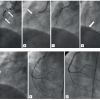

Even after successful wire passage across a chronic total coronary occlusion (CTO), PCI is sometimes limited similarly by the inability to pass with a balloon catheter . In this particular setting ELCA is a valuable option since, in contrast to rotational atherectomy, it can be advanced along standard guidewires ( Figure 7 parts 1 and 2). The laser can create a channel through the CTO which allows a balloon catheter to pass afterwards in order to facilitate final vessel reconstruction by stent implantation [2424. Bilodeau L, Fretz EB, Taeymans Y, Koolen J, Taylor K, Hilton DJ. Novel use of a high-energy excimer laser catheter for calcified and complex coronary artery lesions. Catheter Cardiovasc Interv. 2004;62:155-61. , 2525. Gruberg L, Mehran R, Dangas G, Hong MK, Mintz GS, Kornowski R, Lansky AJ, Kent KM, Pichard AD, Satler LF, Stone GW, Leon MB.. Effects of plaque debulking and stenting on short term and long-term outcomes after revascularization of chronic total occlusions: comparison of debulking (laser or RCA) plus stenting alone in the treatment of chronic total occlusions. J Am Coll Cardiol. 2000;35:151-156. ]. Meticulous attention should be paid to a correct distal intraluminal wire position before ELCA is performed in order to avoid perforations.